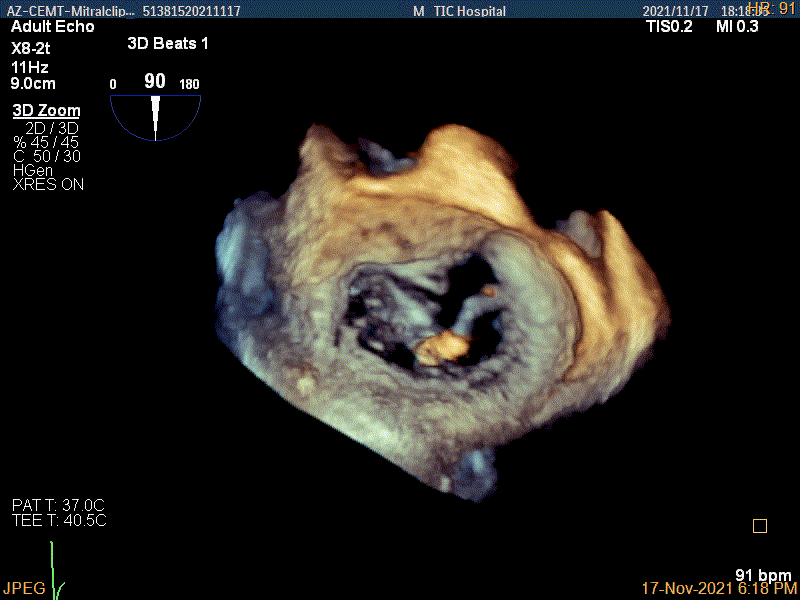

3D视图下进第二个夹子并建立trajectory

将第二个夹子置于第一个夹子内侧尽量靠近,并调节Rotate呈尽量平行关系

成功抓捕内侧残余脱垂区域瓣叶

第二个夹子夹闭后,反流量明显减少

3D视图两个夹子近似并排排列

3D-color视图下两个夹子间少量残余反流